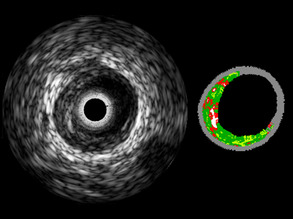

Sound Circulation

10